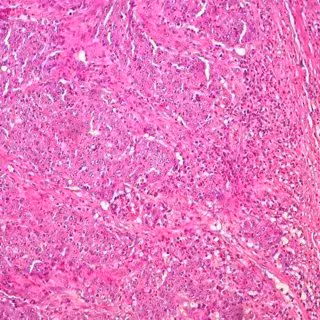

Cáncer de colon

El Instituto de Investigación Sanitaria del Hospital Clínico Universitario de Valencia-INCLIVA y el Servicio de Oncología de este Hospital han participado en un ensayo europeo para estudiar la eficacia del anticuerpo Lumretuzumab como tratamiento en pacientes con tumores que expresan el oncogen HER3, que está considerado como un factor de pronóstico negativo en todo tipo de tumores cancerígenos, en particular, de mama, ovarios, pulmón y colon.

Al respecto, ha destacado que los estudios previos en modelos preclínicos ya habían demostrado que el lumretuzumab "disminuye la regulación del oncogen HER3 en los tejidos de los tumores". Además, los resultados del ensayo en pacientes apuntan que el uso de este anticuerpo "disminuye la expresión de los niveles de HER3, limitando el progreso de la enfermedad " y ello con "efectos secundarios escasos" y una tolerancia "correcta".